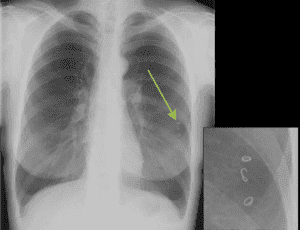

Самый простой и достаточно надежный метод определения наличия паразитов в легких рентген. Рентгенографическое исследование позволяет обнаружить следы жизнедеятельности глистов, самих гельминтов, кисты, образующиеся при эхинококкозе.

Если существует вероятность спутать паразитарное заболевание с пневмонией или туберкулезом, проводят дополнительные исследования:

- При цистицеркозе личинка-цистицерк свиного цепня фиксируется в легочной интерстициальной ткани, и усиленно там размножается. Около нее создается фиброзная капсула, охваченная лимфоцитарной инфильтрацией, и образуются многочисленные круглые или овальные, диаметром 1 или 2 см, отдельные пузырьки. Вначале заболевания в прилегающей к очагам легочной паренхиме изменений не наблюдается, но затем развивается деформация структуры легочной ткани. Если пузырьки образуются под плеврой, то происходит очаговое уплотнение реберной и междолевой плевры. Когда же произойдет гибель цепня (через 2-3 года) очаги кальцифицируются.